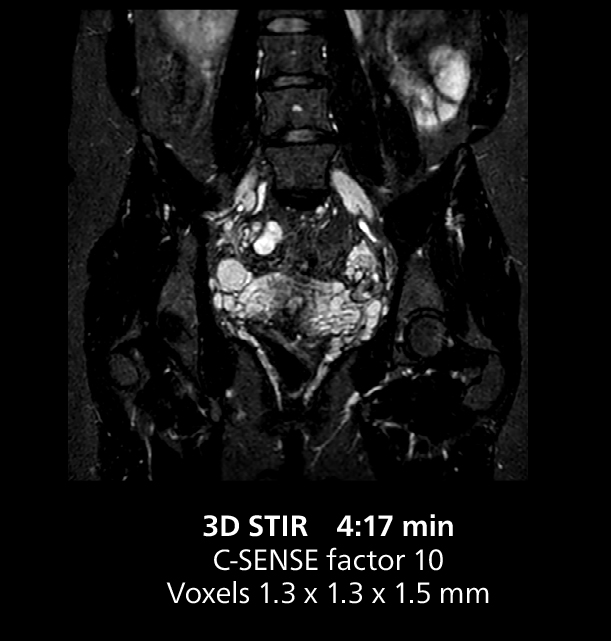

The isotropic high resolution 3D sequence in this MRI case allows for reformatting to obtain other orientations with high quality. Acquired on the MR 5300 system.

Dr. Gellée highlights the robust free-breathing scans as “the feature that makes the biggest difference in my daily work. The 3D free breathing sequences are very reproducible, and the axial acquisition is very good. For example, in endometriosis, which is one of my focus areas, it provides high contrast and good resolution so that I can see small details. We also use free breathing for liver and pancreas imaging. In multi-phase liver studies, 4D Free Breathing delivers 3-second temporal resolution, making a dynamic scan with more than one arterial phase possible.”

This MRI case illustrates good resolution and imaging quality obtained within reasonable scan times using the MR 5300 1.5T system with the anterior torso cardiac coil that allows use of a large field of view (FOV).